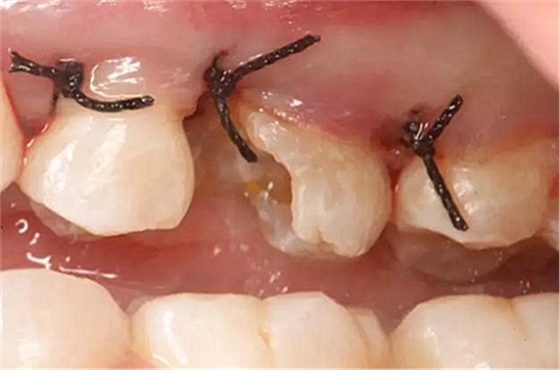

患牙遠(yuǎn)中邊緣嵴完整,強(qiáng)度沒有降低,故擬保留遠(yuǎn)中邊緣嵴,高嵌體修復(fù)。首先去除腐質(zhì)及原墊底材料,流體樹脂+3M Z350XT樹脂墊底。局麻下行冠延長手術(shù)。在此需要提及個人的一個觀點(diǎn)。冠延長手術(shù)原則上要求3-6個月以上才能永久修復(fù)。但是個人喜歡后牙肩臺建立在齦上,所以修復(fù)后的修復(fù)體邊緣位于牙齦上方1mm,對牙周的愈合影響較小(如果為齦下邊緣則要慎重),故該患者術(shù)中按照齦上邊緣的設(shè)計(jì)進(jìn)行冠延長手術(shù)。以下為術(shù)中:

改良垂直褥式縫合關(guān)閉傷口,傷口無明顯滲血,高嵌體預(yù)備完畢后,硅橡膠取模,見邊緣清晰。灌注模型,模型上3MZ350XT分層堆塑高嵌體。